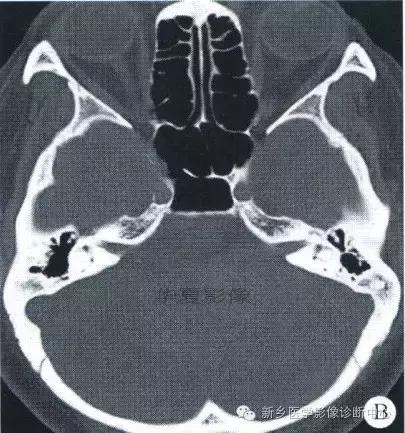

中枢神经系统内原发性黑色素瘤少见, 因脑和脊髓的软脑( 脊) 膜及蛛网膜上含有黑色素细胞, 黑色素可发生于软脑( 脊) 膜的任何部位,故其发生部位常位于脑( 脊髓) 表面, 沿软脑膜生长; 而继发性黑色素瘤同一般转移性肿瘤, 常位于灰白质交界区。

影像表现:常表现为短 T1 高信号, 短T2WI 低信号,又因为黑色素瘤是富血管性肿瘤, 增强扫描常表现为明显强化。

★但少数肿瘤也不具备上述典型信号特征,主要原因是肿瘤内黑色素量多少影响。只有当黑色素瘤中黑色素细胞超过一定含量( ﹥ 10% ) 时, 才会出现黑色素瘤的典型MRI表现; 不典型的黑色素瘤因其黑色素含量较少,不足以缩短T1、T2弛豫时间,而表现为长T1低信号、长T2高信号。

依据黑色素瘤的不同 MRI 影像表现将其分为 4 种类型: ( 1) 黑色素型。该黑色素瘤因含有丰富的黑色素颗粒, MRI表现较典型,即短 T1 高信号,短 T2 低信号。( 2) 无黑色素型。因该类黑色素瘤不含黑色素颗粒或含量较低,MRI 表现为长 T1 低信号,长 T2 高信号; ( 3) 混合型。黑色素型和非黑色素型两者的混合; ( 4) 出血型。表现为血肿不同时期的信号特征, 该黑色素瘤 MRI增强扫描表现为不均匀环状或弥漫性强化